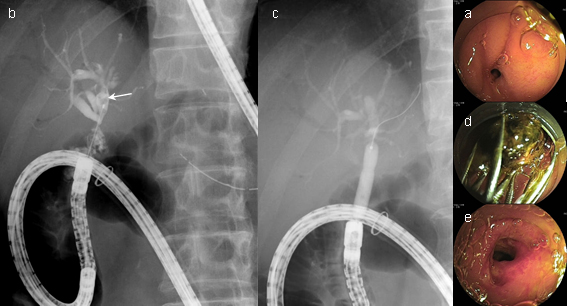

ダブルバルーン内視鏡(図1)は、内視鏡先端とオーバーチューブ先端にバルーンが装着されていて、これら二つのバルーンで腸管を軽く把持して短縮しながら腸管内を内視鏡が挿入される構造になっています。シングルバルーン内視鏡(図2)は、オーバーチューブ先端のみにバルーンが装着されていて、内視鏡には装着されていませんが、基本的な挿入原理は同じです。

3. バルーン内視鏡を用いたERCPの実際